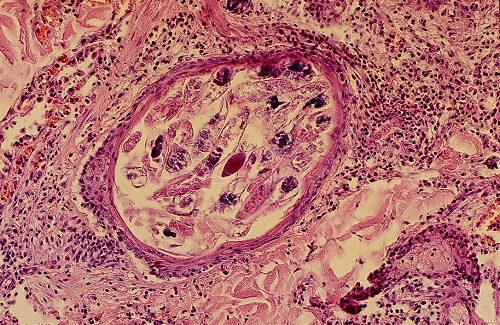

Histologie.

D.canis

vit dans les

follicules pileux

, accessoirement les

glandes sébacées

.